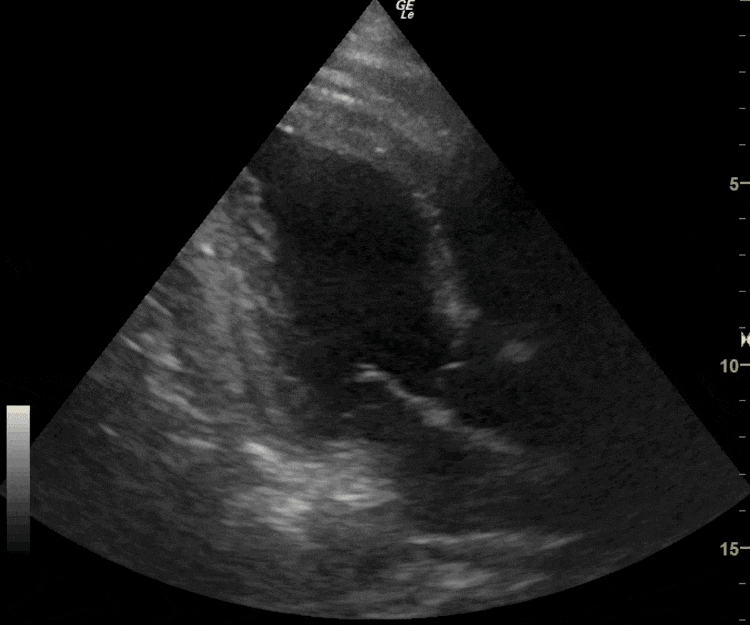

▲患者冠脉造影

▲患者术后心超影像